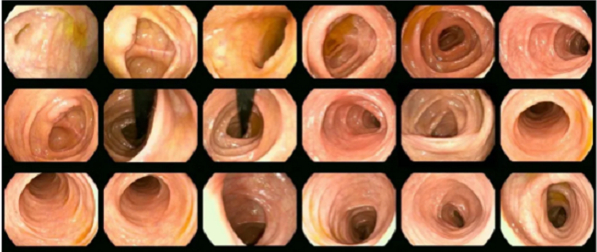

此次“胃肠镜全套检查福利价”活动,天兴胃肠使用的是奥林巴斯NBI无痛电子胃肠镜技术,此项技术被誉为消化道疾病诊疗金标准,其成功将NBI窄带成像技术、4K超高清影像系统等技术联合应用。

对于普通内镜观察不到的微小血管结构(毛细血管、集合小静脉、癌新生血管等)及黏膜表面微细结构(隐窝边缘上皮、隐窝开口、隐窝间部等)可以清晰地观察到,取得了显著的临床效果。